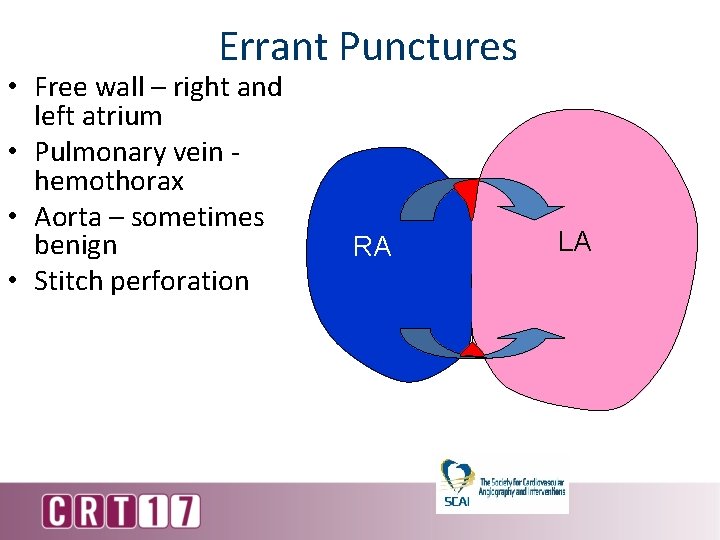

Errant Punctures • Free wall – right and left atrium • Pulmonary vein hemothorax • Aorta – sometimes benign • Stitch perforation RA LA